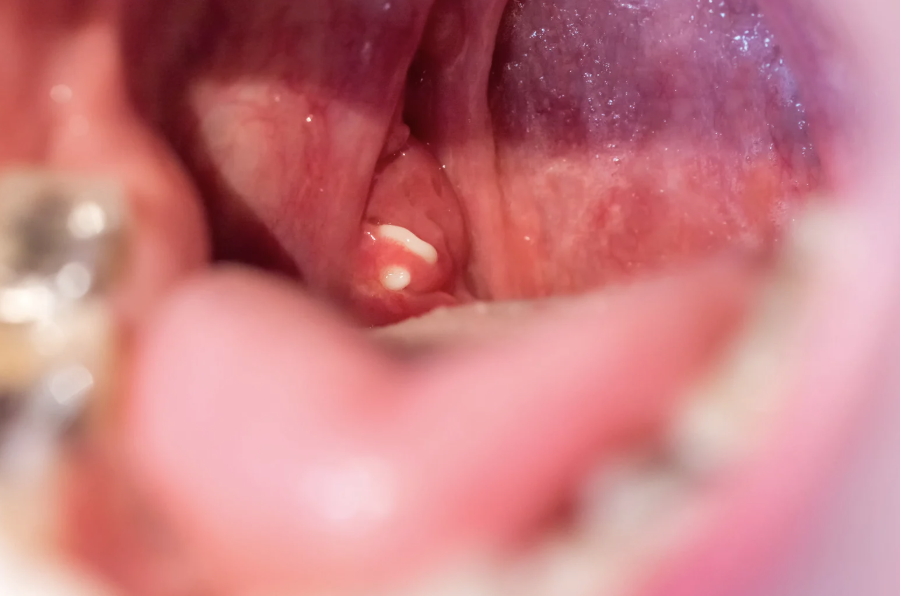

Tonsillitis is the inflammation of the tonsils. Tonsils are two oval-shaped pads of lymphoid tissue located at the back of the throat and form an important part of the immune system. They act as filters by trapping bacteria and viruses that could otherwise enter the airways and cause infection. Tonsils also help the body by producing antibodies to fight infections.

Peritonsillar Abscess

Collection of pus near the tonsil causing intense pain, swelling, and difficulty opening the mouth.